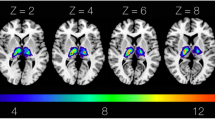

Patient AA is a 42-year-old man, examined 1.5 years after a left hemisphere CVA that affected the anterior parts of the superior and middle temporal gyri, as far posteriorly as the sulcus acousticus (see Figs. 1 and 2). Lesion analysis showed that the cortex of the temporal pole as well as the cortex posterior to the sulcus acousticus, i.e. the classic dorsal posterior temporal language region (Wernicke’s area), was completely spared. In addition, there was specific damage to the pars triangularis of the IFG where granular area 45 lies with complete sparing of the pars opercularis (dysgranular area 44) and no other damage in the frontal lobe (see Fig. 2). There was no damage to the occipital lobe or the adjacent occipito-temporal region. This is important because at times impairments related to the ventral language system, namely the anterior temporal cortical region, have been incorrectly attributed to damage of the multicomponent so-called inferior fronto-occipital fasciculus. Damage was also observed in the internal capsule, external capsule, parts of the basal ganglia, and the anterior insula. DTI analysis showed decreased fractional anisotropy (FA) in the TFexcF (Table 1) which is the white matter connection between the anterior lateral temporal region and the frontal cortex, and on the IFG specifically with the pars triangularis where area 45 of Broca’s region lies. Thus, the CVA lesion affected selectively the ventral anterior temporal language system.

The lesion appears at Y35 and continues as far as Y20, including a part of the pars triangularis (area 45) and the white matter below (see Y26, Y21). At Y19, the lesion also includes part of the caudate, the adjacent internal capsule (IC), the external capsule (EC), and the temporo-frontal extreme capsule fasciculus (TFexcF), just below insular gyrus Brevis I (GBI). Subcortically, there is damage to the claustrum, putamen, and the anterior part of the insula (GBI) under which courses the TFexcF. From Y15 to Y7, the lesion includes a small part of the anterior STG. Moving on posteriorly, between Y3 and Y-3, one can observe damage to the TFexcF which courses between the claustrum and the anterior insula (gyrus Brevis III; GBIII), the STG and a small part of MTG, including both banks of the superior temporal sulcus (sts) (see Y0). At Y-7, one observes that the lesion is located anterior to the level of the sulcus acousticus (sa) that lies on the lateral STG (see also Fig. 2). Subcortically, the lesion includes part of the caudate, IC, EC, TFexcF between the claustrum and insular gyrus Brevis III and gyrus Longus I & II, STG, sts and the whole MTG. The temporal lesion is visible as far posterior as Y-15 where it is restricted to the insula, caudate, putamen, claustrum, EC, TFexcF, and at Y-19 to putamen and lower insula, leaving Heschl’s gyrus and the surrounding temporal areas completely spared. Posterior to Y-20, no lesion is detected. Brain areas are topologically defined according to the atlas of the morphology of the human cerebral cortex in the MNI Stereotaxic Space67. aalf ascending anterior ramus of the lateral fissure; GBI gyrus brevis I of insula; GBIII gyrus brevis III of insula; GLI gyrus longus I of insula; GLII gyrus longus II of insula; half horizontal ascending ramus of the lateral fissure; HG Heschl’s gyrus; IFG:Tr inferior frontal gyrus, pars triangularis; IFG:Op inferior frontal gyrus, pars opercularis, Or pars orbitalis; Tr pars triangularis; ifs inferior frontal sulcus; lf lateral fissure; MFG middle frontal gyrus; MTG middle temporal gyrus; PoG postcentral gyrus; PrG precentral gyrus; sts superior temporal sulcus; ts triangular sulcus.

The cortical lesion is marked by the red color and occupies the superior and middle temporal gyri (STG and MTG) anterior to the sulcus acousticus (sa), as well as the pars triangularis (area 45) of the inferior frontal gyrus. Note that the posterior parts of the superior and middle temporal gyri (i.e. the classical Wernicke area) and also the cortex of the pars opercularis (area 44) are spared. Thus, the lesion is restricted to the ventral language stream. Subcortically, the lesion is represented by the pale pink color. The lesion of the patient was reconstructed in MNI stereotaxic space and projected on the standard average MNI brain65,66. Abbreviations: aalf ascending anterior ramus of the lateral fissure; half horizontal ascending ramus of the lateral fissure; ifs inferior frontal sulcus; lf lateral fissure; MTG middle temporal gyrus; Op pars opercularis (area 44); sa sulcus acousticus; STG superior temporal gyrus; sts superior temporal sulcus; Tr pars triangularis (area 45); ts triangular sulcus.